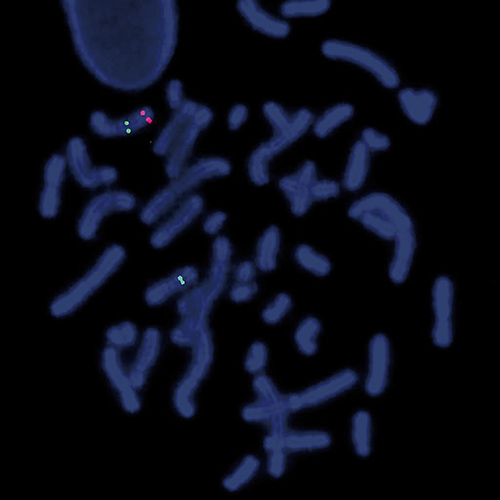

7q- (7q22; 7q36) hybridized to patient material showing a 7q36 deletion (1R2G). Image kindly provided by Prof. Jauch, Heidelberg.

Loss of a whole chromosome 7 or a deletion of the long arm, del(7q), are recurring abnormalities in malignant myeloid diseases. Most deletions are interstitial and there are two distinct deleted segments of 7q. The majority of patients have proximal breakpoints in bands q11-22 and distal breakpoints in q31-36. The CCAAT displacement protein CUX1 gene region is located in the 7q22 critical region. The 7q- specific FISH probe is optimized to detect copy number of 7q at 7q22 and at 7q36 simultaneously in a dual-color assay.